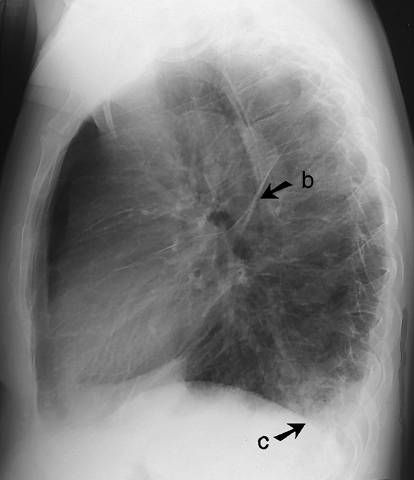

Kuva 1. Interstitiaalinen ödeema keuhkoissa (etukuva). Septaaliviivat (a) näkyvät parhaiten keuhkojen etukuvan ala-lateraaliosissa, pleuraa kohti kohtisuorina 1–2 cm:n mittaisina viivoina. Tilaan liittyy pleuraneste (c). Sivukuva: ks. «Interstitiaalinen ödeema keuhkoissa (sivukuva)»1.